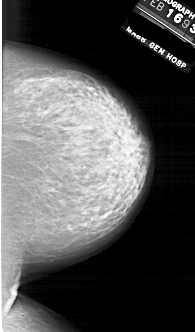

A_1854_1.LEFT_CC

LEFT_CC LINES 6871 PIXELS_PER_LINE 3991 BITS_PER_PIXEL 12 RESOLUTION 43.5 OVERLAY

FILE: A_1854_1.LEFT_CC.OVERLAY

TOTAL_ABNORMALITIES 1

ABNORMALITY 1

LESION_TYPE CALCIFICATION TYPE PLEOMORPHIC DISTRIBUTION CLUSTERED

ASSESSMENT 4

SUBTLETY 2

PATHOLOGY BENIGN

TOTAL_OUTLINES 1

BOUNDARY